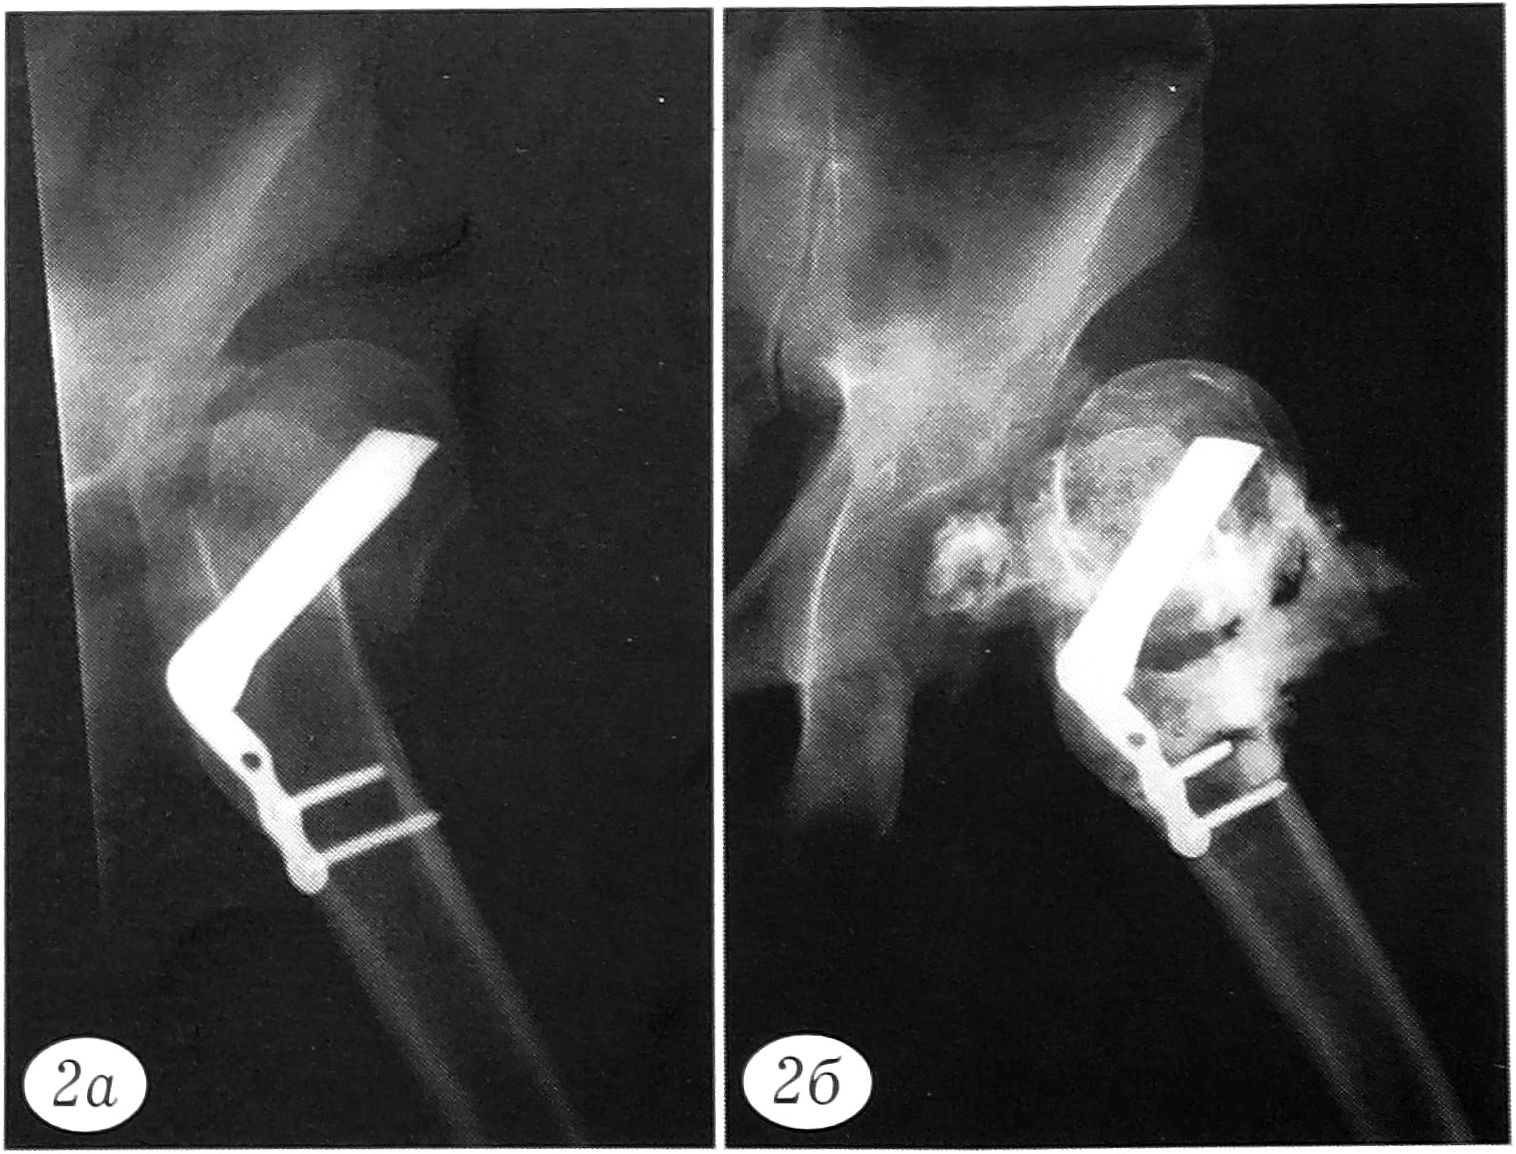

Рис. 2. Рентгенограмма (а) и фистулограмма (б) больного У. 36 лет при поступлении. Ранее по поводу перелома шейки левой бедренной кости был выполнен остеосинтез трехлопастным гвоздем с пластиной Лена. Через 10 дней после операции развился гнойно-воспалительный процесс. Через 1 мес выявлены нестабильность конструкции, остеомиелит проксимального отдела бедренной кости. Поступил через 3 мес после остеосинтеза.